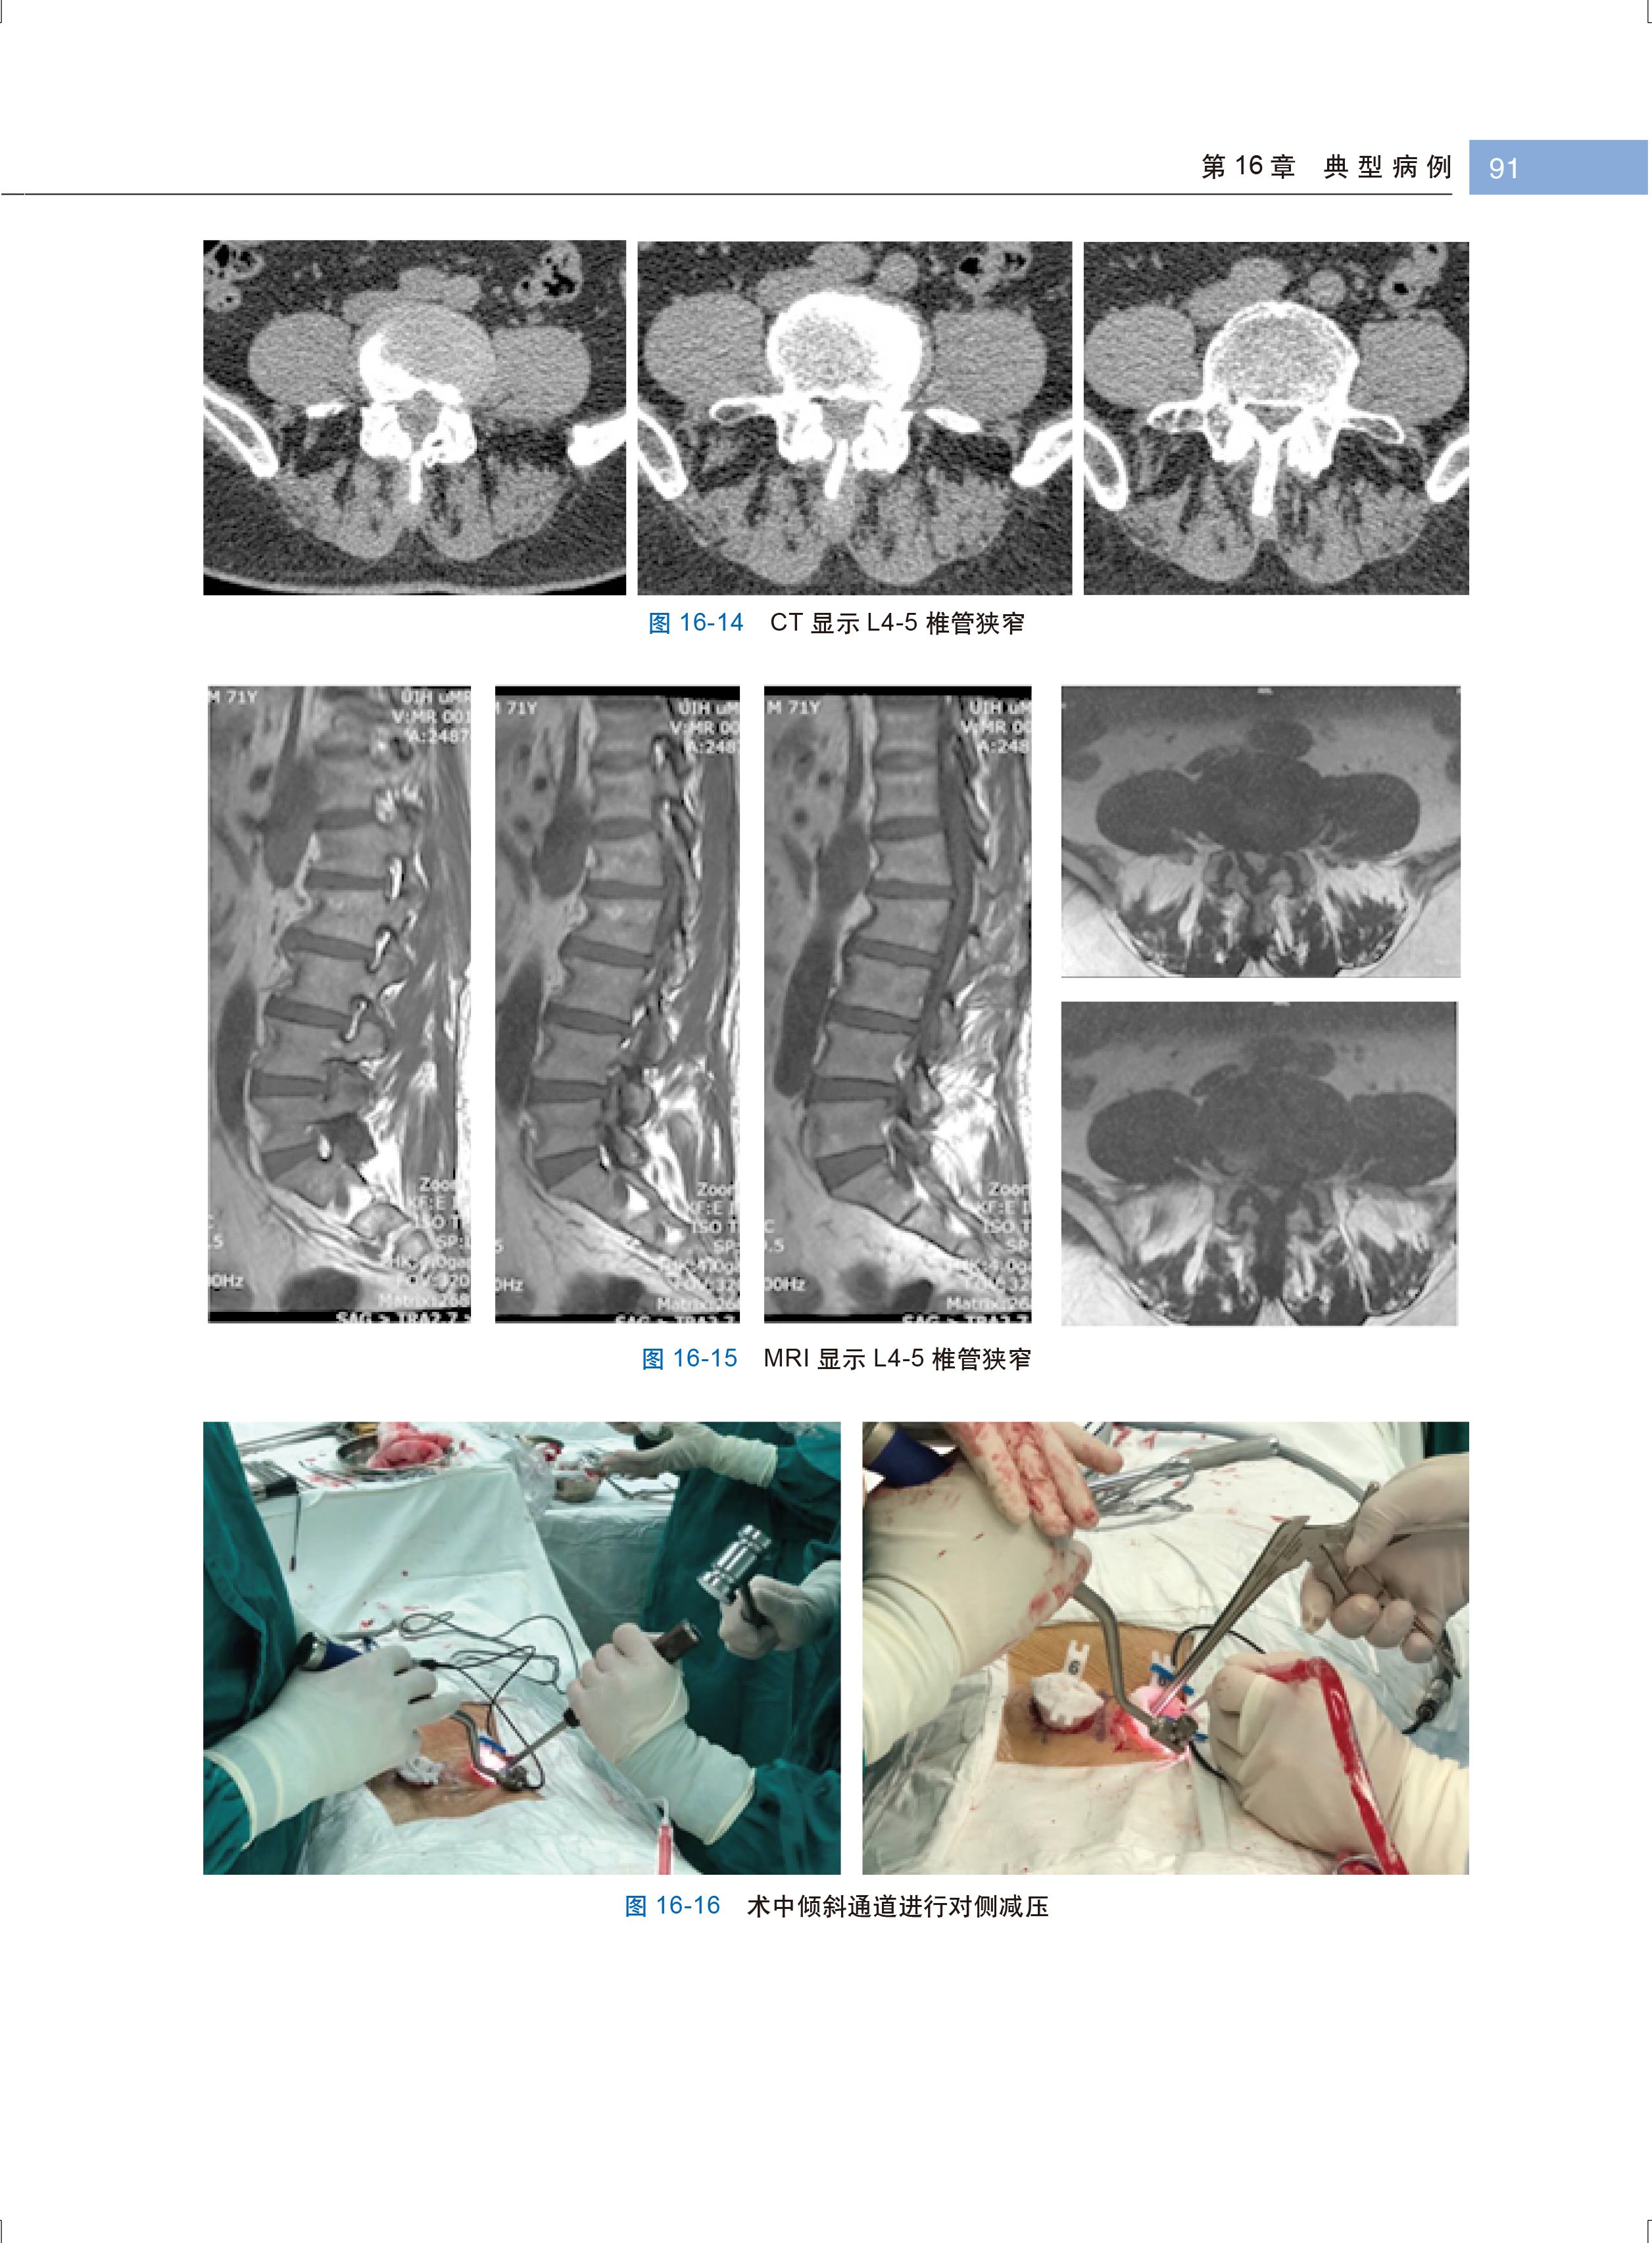

病例三 MIS-TLIF 手术治疗腰椎管狭窄症 89